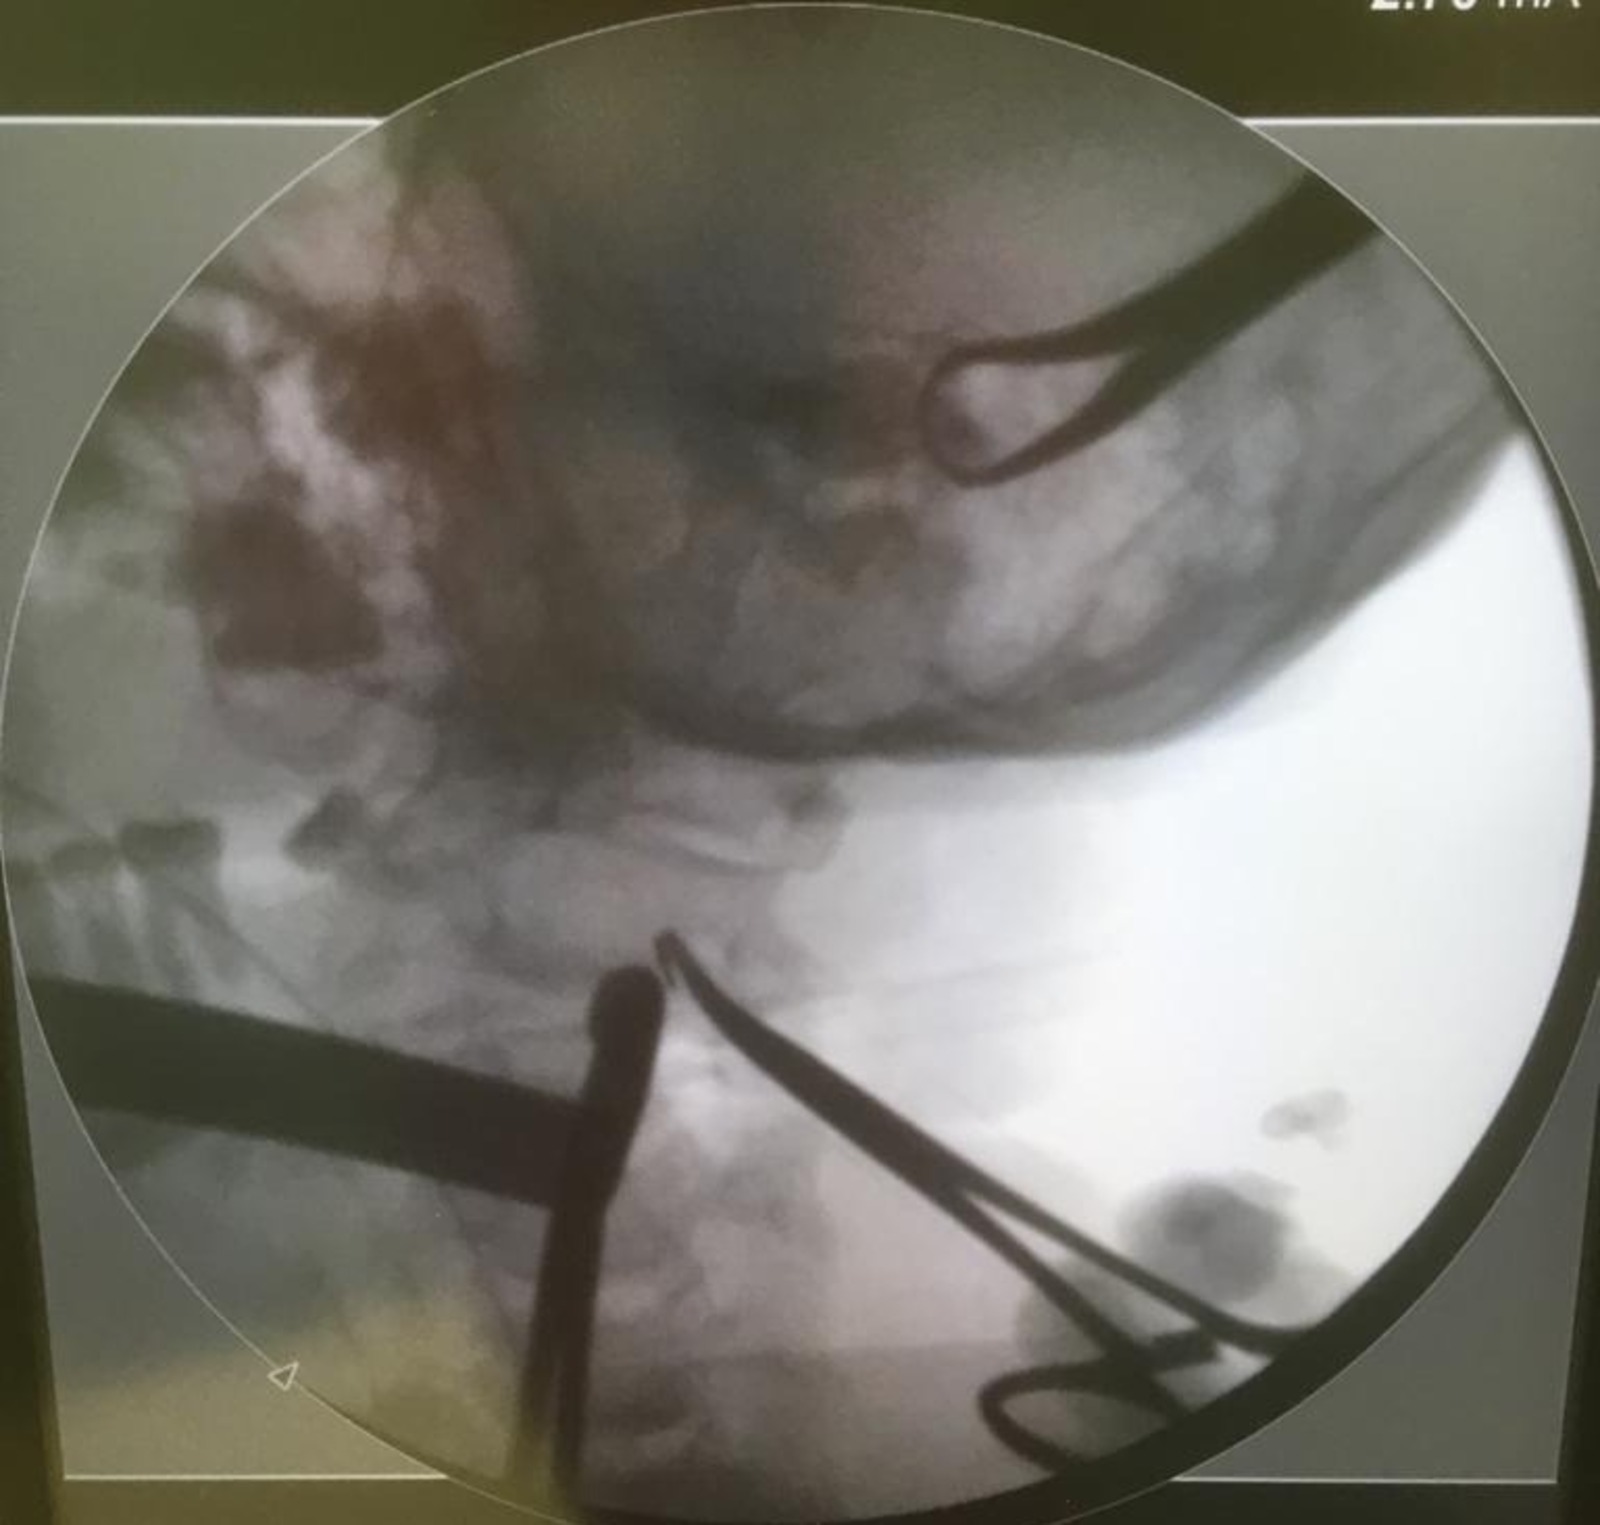

Уфимские хирурги больницы № 21 прооперировали участника СВО, удалив осколок гранаты с  наружной стенки сонной артерии. Как сообщили « Башинформу » в пресс-службе медучреждения, мужчина получил ранение в шею в Артемовске. В военном госпитале ему была проведена первичная хирургическая обработка ран. Однако, в связи с риском повреждения артерии, врачи не решились на удаление одного из осколков. Во время отпуска пациент обратился к уфимским специалистам.

«Оперировал бойца заведующий отделением челюстно-лицевой хирургии Азат Сулейманов, ему ассистировал хирург Ильдар Туктаров. В операционной бригаде работал анестезиолог Раил Мараканов, операционная сестра Инзиля Акхамова, анестезистка Зухра Ахметова. Осколок сравнительно очень мелкий: примерно 4 миллиметра в ширину и длина 9 мм, поэтому хирургическое вмешательство проведено под рентген-контролем и в опербригаду включен рентген-лаборант Рустам Хайруллин», — рассказали в больнице.

По словам Азата Мудасировича и Ильдара Рашитовича, осколок маленький, его буквально искали с помощью рентгена. Но хотя и мелкий, но бед мог он натворить больших: повредить кровеносный сосуд, вызвать нагноение.